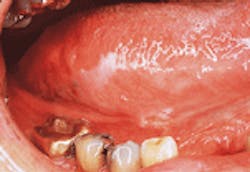

Erythroplakia

- Erythroplakia. The term erythroplakia is a clinical term that is used to describe a lesion that appears as a "red patch." The erythroplakia appears as a red, flat, well-defined area with a texture that resembles velvet.